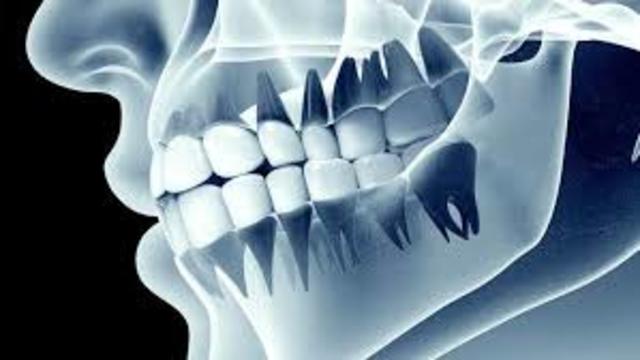

El doctor Montoya Flórez, padre de la cirugía en Colombia, trajo a Medellín el primer equipo de rayos X con el cual se realizó la primera radiografía en Colombia.

El doctor Emilio Jaramillo (1877-1949) abrió el primer consultorio radiológico en Medellín en 1925. Se había graduado a principios de la década del 20 con la tesis "Radiología".